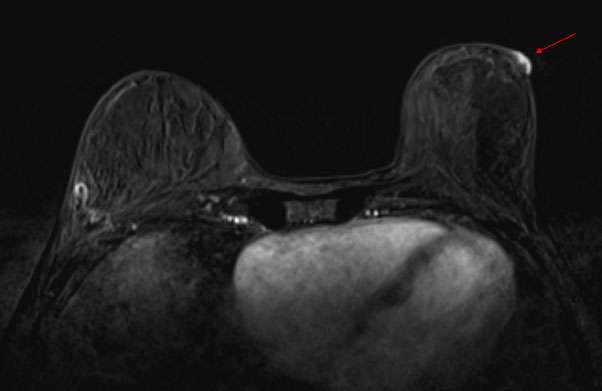

Breast MRI is highly sensitive for the detection of breast cancer and may be used in patients with Paget’s disease of the breast to establish the extent of disease. MRI may show thickening of the nipple/areola, asymmetric abnormal enhancement of the nipple/areola, enhancing masses, and linear/segmental non-mass enhancement.